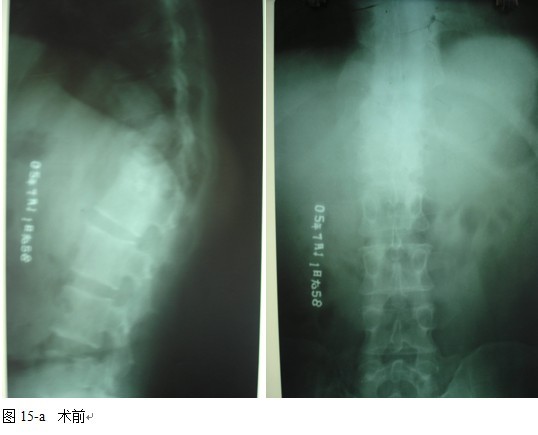

本组46例中男28 例,女18 例。年龄17~67岁,病程6 个月~7年,平均11.3 个月。本组患者均为 L1~S1腰段结核。病灶累及2 个椎体31例(L1-2 6例, L2-3 8例,L3-4 10例,L4-5 5例,L5-S1 2例),3 个或3 个以上椎体15例。合并腰大肌脓肿23列,所有患者均有腰背部疼痛,活动受限,双下肢感觉麻木19例,会阴部感觉减退12例,双下肢肌力减弱12例,腱反射减弱12例,术前后凸角(Cobb 角) <30°者12例, 30°~60°者28 例, >60°者6 例,Cobb角平均32.3°4例患者是二次手术。术前均行X线片、CT或者MRI检查。术后病理检查确诊为脊柱结核。

2.2 手术方法

图11-a术前